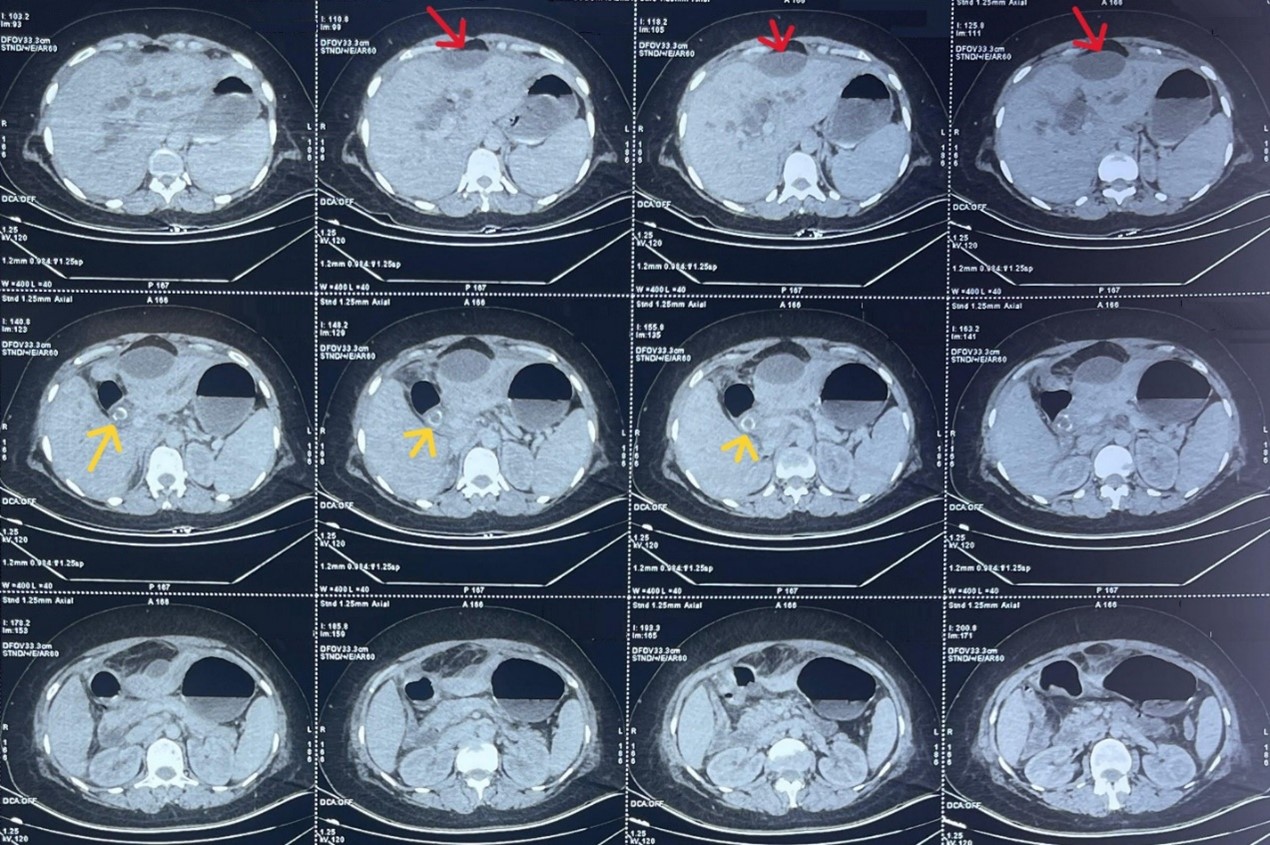

Computed tomography of the abdomen revealed two large stones within the common bile duct, responsible for upstream dilatation of the intrahepatic bile ducts. The gallbladder was not visualized. A lentiform subcapsular fluid collection exerting scalloping on segment IV was noted, measuring 60 × 30 mm, associated with marked fat stranding around the lesion and the gallbladder bed. The liver was of normal volume with regular contours and no focal lesions. Minimal perihepatic fluid was present, with mild thickening of the peritoneal layers.

Overall, the CT findings suggested a subhepatic collection related to a perforated or scleroatrophic gallbladder, complicated by common bile duct lithiasis.

Figure 1: Computed tomography image showing a subhepatic fluid collection (red arrow) and stones within the common bile duct (yellow arrow).